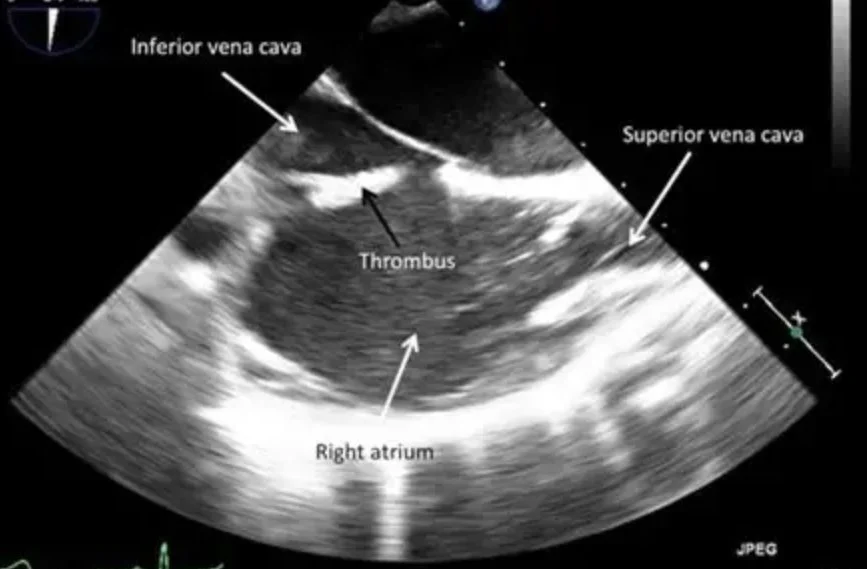

The main reason for doing a TEE first is to check for blood clots in the heart.

If a clot is present and cardioversion is done, the clot could travel to the brain and cause a stroke.

TEE helps doctors make sure it is safe to proceed with cardioversion by ruling out these clots